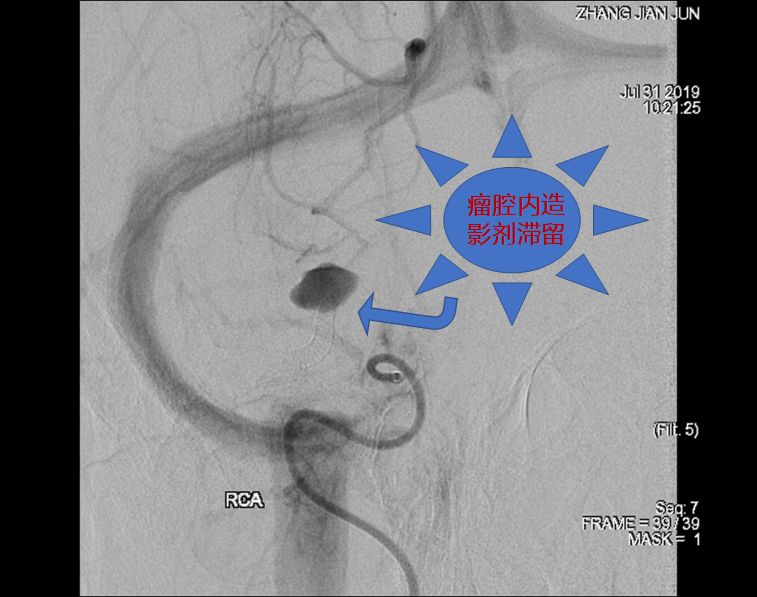

2、术后18小时急诊DSA(图六)。

图六

DSA术前后对比(图七)。

图七

术前讨论:如何使患者获得最大受益?因为是夹层动脉瘤,如果填圈治疗,一是外侧豆纹动脉会即刻闭塞,更易引起临床症状;二是填圈治疗有使夹层动脉瘤撕开、出血的风险。所以经讨论我们决定采取一种折中方案,只放密网支架而不填圈的手术方式。我们希望通过密网支架的支撑,使夹层动脉瘤慢慢消失。通过慢性闭塞,给夹层动脉瘤上方的豆纹动脉部位一个代偿血管增生的时间,减少患者发生偏瘫的概率。经过精准测量后,选择合适支架。术中手术顺利,术后进行血管三维重建,密网支架放置良好,贴壁良好,可以清晰的看到豆纹动脉。术后患者回到病房后,一般情况良好。术后18小时后患者出现言语含糊、左侧中枢性面舌瘫,左侧肢体偏瘫,CT排查出血后考虑是患者夹层动脉瘤上方的豆纹动脉闭塞引起的症状。立即行全脑血管造影,发现豆纹动脉确实消失。确定豆纹动脉消失是引起患者临床症状的一个主要原因。这是天坛医院第一例在密网支架植入术后第一天就复查造影的患者。造影结果让我们惊喜的发现,密网支架治疗后,不到18个小时,患者的动脉瘤几乎完全消失。从而证明,我们的手术通过精准测量,选择合适的密网支架对夹层动脉瘤的治疗效果以及夹层的修复效果是非常明显的。当然,患者出现穿支动脉的闭塞,是我们术前充分考虑的,且无法避免的一个并发症。术后给予神经康复,高压氧治疗,患者有明显的好转趋势。我们希望通过后续的康复治疗可以使患者的生活接近正常,同时我们也在密切随访患者,希望患者动脉瘤完全消失,并且正常生活。